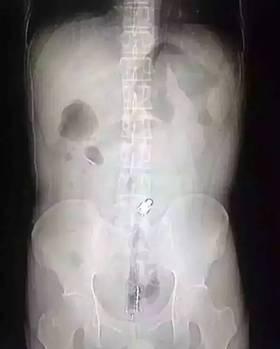

“因为物体边缘比较光滑,手术的时候,我们两个人合作,一个人顺着肚子一点点推,推到肛门口,我把异物拿了出来,大概花了十分钟时间。”郁峰说,这名男子运气算好的,因为根据拍片检查,当时那根振动棒已经挤到了肚脐的部位,情况其实已经相当危险。医生提醒“那根振动棒有20公分,人的直肠只有18公分,它的长度已经超过直肠了,到达乙状结肠,会引起肠子破裂坏死,如果破了就会有生命危险。”

男子为寻刺激将20厘米塑料棒塞入肛门险致命

2014年03月25日,江西省南昌市,一名中年男子在家中玩时,不慎将一约20厘米长的硬质塑料棒滑进肛门内。医生在手术室费时一个多小时,才将这支深沉在体内的塑料棒取出。据悉,异物经肛门进入体内后,因为患者无法进食也无法排便,腹腔会发生膨胀,如不及时取出,将会影响到患者的生命。